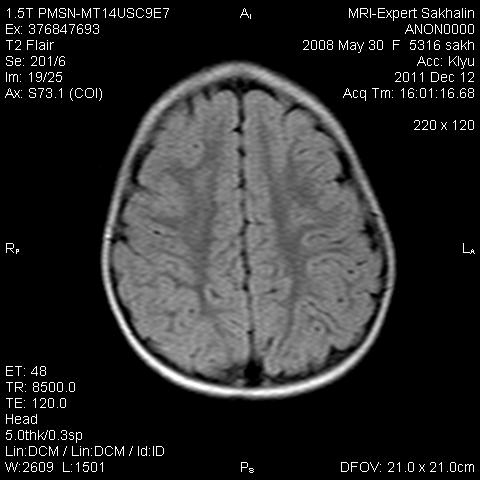

Девочка 3 года.В анамнезе -родовая травма-внутрижелудочковые кровоизлияния 1-2 ст.Задержка психического развития.Со слов мамы, "бывают истерики, хватается ручками за голову, особенно затылочную часть".Как интерпретировать изменения в желудочках, в задних рогах?Ликворную кисту ЗЧЯ отметила.

Здравствуйте! Извините что вклиниваюсь в вашу дискуссию. В дополнение ко всему сказанному мне показалось что для трехлетнего ребенка желудочки несколько великоваты, больше слева. Ликворные пространства не симметричны, опять больше слева. В складочках мозга мелкие, пока, кисточки. Может быть попробовать исключить церебральный арахноидит? Пункцию делали?

Коллеги, в рамках ликбеза: а такое (некоторое) расширение субарахноидального пространства (не вполне характерное для 3-летнго ребенка), расценивается как гидроцефалия (заместительная, открытая, последствие ишемически-гипоксического синдрома) или нет?

В данном исследовании я не отмечала наружную гидроцефалию.